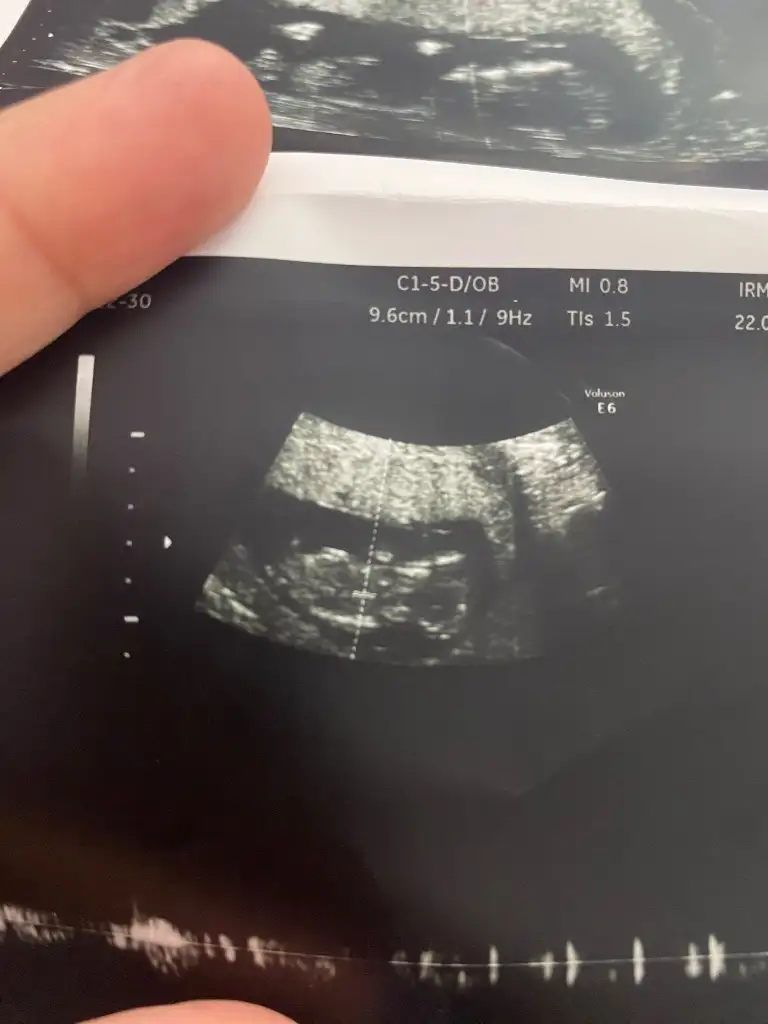

13 hafta cinsiyet nedir sizce yorumlar musunuz lütfenkız gibi

Kız gibi canım13 hafta cinsiyet nedir sizce yorumlar musunuz lütfen

Tabi öyle doktorlar dahi yanılıyor ama merak işteKız gibi canım

13 haftalik bakarmiisniz karindanKızlar bebişlerinizin ultrason resimlerini ve cinsiyetini kaçıncı haftada olduklarını yazında kendi ultrason resimlerimizle kıyaslayıp fikirde bulunalım. Nub teorisi, kafa şekli, kemik yapısından cinsiyet teorileri tutuyor mu bakalım bir![]()